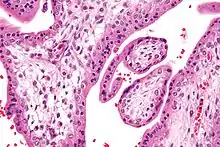

Micrograph showing chorionic villi. Intermediate magnification. H&E stain. Micrograph showing chorionic villi. Very high magnification. H&E stain.

Micrograph showing chorionic villi. Very high magnification. H&E stain. Section through the embryo.